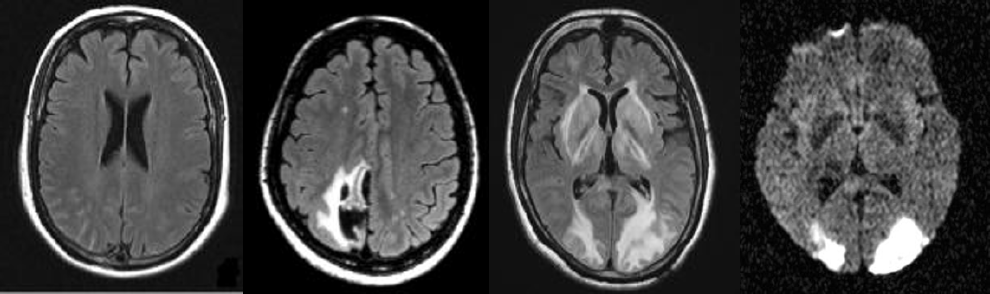

團隊發現RCVS患者的腦血管攝影中,可以看見血管一節節收縮的痕跡,收縮的狀況由小血管慢慢移到中央血管區,因此剛開始檢查時很難看見。RCVS會引起嚴重的併發症,例如可逆性腦後方白質病變或腦水腫達9-38%、缺血性腦梗塞達4-54%,以及腦出血可能高達20%,必須及早診斷。

左側是腦部血管收縮的圖,白色箭頭是血管收縮處,黑色箭頭指的是收縮後面有時伴隨血管擴張,因此血管看起來像念珠狀一節一節,右側則是恢復成正常的樣子。(圖/陳世彬提供)

榮陽頭痛研究團隊是全台第一個釐清RCVS臨床表現、建立檢查與治療標準流程、找出併發症的團隊,並開發新影像技術協助診治和探討病生理機轉,在RCVS領域中的研究成果可說是世界第一。